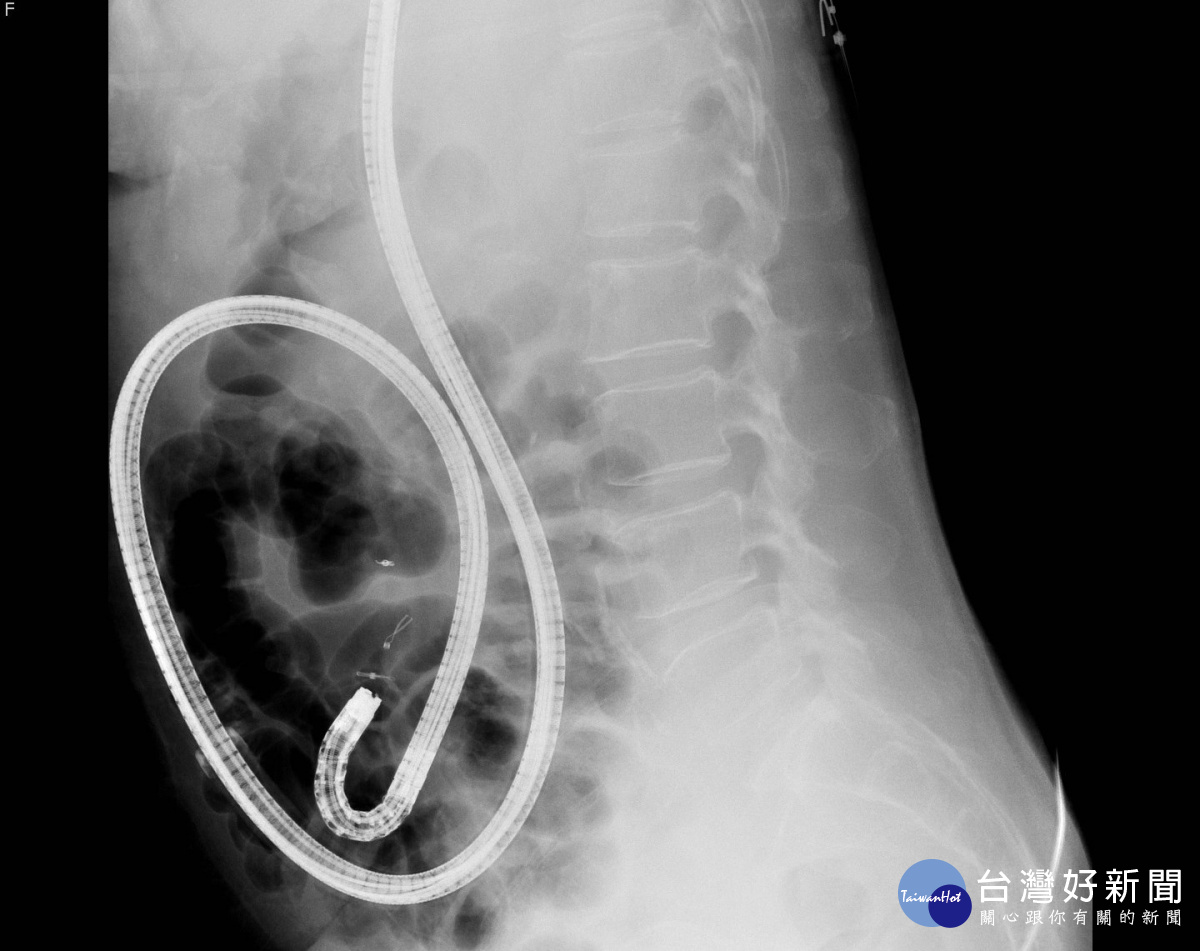

單氣囊輔助小腸鏡 新竹馬偕竹苗地區率先引進

年近70歲的女性患者有長期貧血病史,最近因排出大量黑便還暈倒,至新竹馬偕醫院檢查。結果發現患者血紅素只剩9.4g/dL(正常女性為11-16g/dL),醫師根據臨床症狀,懷疑患者可能因消化道出血導致貧血,但包括胃鏡、大腸鏡、電腦斷層血管攝影和核子醫學胃腸道紅血球掃描等檢查都未發現明確出血點,最後安排患者接受單氣囊輔助小腸鏡檢查,終於診斷出小腸末端迴盲瓣處有潰瘍出血,病理報告證實為一良性病灶,服用潰瘍藥物後,患者不再解黑便,血色素也逐漸回升到正常範圍,追蹤一年血色素數值均穩定在11.5g/dL左右,患者貧血問題治癒。

為患者進行單氣囊輔助小腸鏡檢查的新竹馬偕紀念醫院胃腸肝膽內科吳政輝醫師解釋,雖然小腸疾患佔消化道疾病不到10%,小腸出血也只佔消化道出血原因5%左右,但當發生胃鏡與大腸鏡都無法確診的消化道病灶時,還是必須安排患者接受小腸鏡檢查。過去竹苗地區並沒有醫療院所有小腸內視鏡檢查設備,須轉送醫學中心檢查,為提供民眾完整的消化道系統照護,新竹馬偕2015年底率先引進醫學中心等級的單氣囊輔助小腸內視鏡檢查設備,至今已成功為近15位患者診治小腸病例,除前述個案外,也有患者有解黑便與貧血的情況,胃鏡、大腸鏡都未發現明顯出血點,最後經由小腸鏡檢查發現小腸空腸處血管顯露且出血,確診病灶後,內視鏡術中也立即為患者進行止血夾介入性治療。

成人小腸長6至7公尺,分十二指腸、空腸和迴腸三部份,長約1至1.8公尺的胃鏡或大腸鏡只檢查得到部分小腸,無法到達小腸深部。傳統檢查小腸的方式為症狀判斷搭配推進式小腸鏡,放射線科的腹部電腦斷層、小腸鋇劑血管攝影,或核醫的胃腸道紅血球掃描,有時甚至得採剖腹術中腸鏡探查才能找出病灶。「推進式小腸鏡最深僅到空腸近端,放射線科、核醫科影像只看得到較大病灶,或檢查當下小腸仍有大量出血時才能顯影」吳政輝醫師說明,手術更可能帶來其他併發症,因此一旦小腸發生疾病,診斷及治療都相對困難。新近的檢查工具小腸膠囊內視鏡及氣囊輔助小腸鏡則提升了小腸影像檢查的臨床應用性;小腸膠囊內視鏡為一內含攝影機的膠囊,患者吞服後,鏡頭會在胃腸道不斷拍攝,再由醫師透過影像檢查病變,雖然有無痛、非侵入性、能完成全小腸觀察的優點,卻也有無法反覆觀察病灶、無法切片取樣或即時治療的侷限。

吳政輝醫師強調,「相較膠囊內視鏡只能診斷卻無法治療,氣囊輔助小腸鏡鏡檢同時,如果發現病灶可以反覆觀察、給予止血、切片取樣、或直接切除腫瘤與息肉;如需進一步手術,也可以標記病灶,方便外科開刀醫師找尋,是能對全小腸進行手術以外檢查及治療的診斷方式」。氣囊輔助小腸鏡可分為雙氣囊或單氣囊輔助,兩者原理類似,以新竹馬偕購置的單氣囊輔助小腸鏡為例,外觀與胃鏡類似,但另附一個有氣囊的外套管,隨氣囊充氣還原,固定小腸壁後往回拉,如同捲袖子一樣,藉由重覆回拉摺疊的步驟深入小腸內部檢查治療。其次,一般胃鏡、大腸鏡檢查時間約10~30分鐘,小腸鏡檢查則需耗時達3至6小時或更久,並要合併經口及經肛門兩種途徑,才可能完成全小腸檢查,但若術前已經由其他影像學檢查定位病灶位置,則可經口或經肛門擇一方式施行針對性檢查或治療。